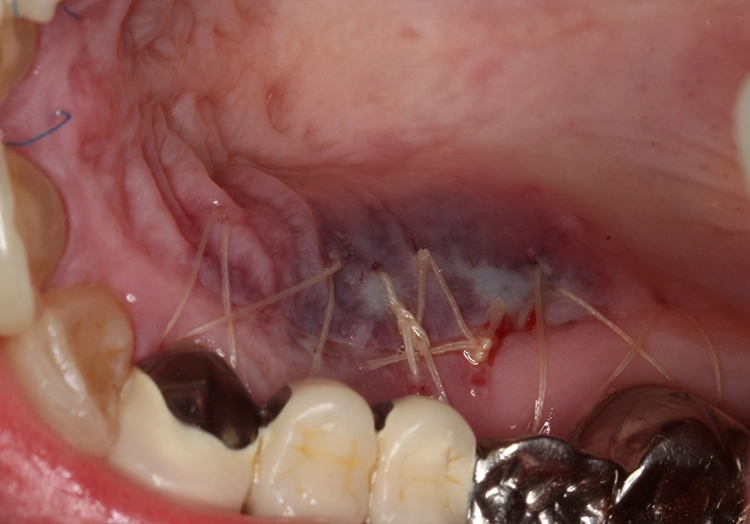

Postoperativ wurde die Patientin angewiesen, für 2 Wochen mit Chlorhexamed zu spülen. Außerdem wurde ihr ein ausdrückliches Putzverbot im Operationsgebiet und die Vermeidung jeglicher mechanischen Irritationen verordnet. Die Nähte am Gaumen (Abb. 6) konnten bereits nach 1 Woche entfernt werden, wohingegen die Nähte am Transplantat erst nach 14 Tagen entfernt wurden. Ab diesem Zeitpunkt konnte die Patientin wieder sehr vorsichtig mit einer sehr weichen Zahnbürste putzen (Abb. 7).